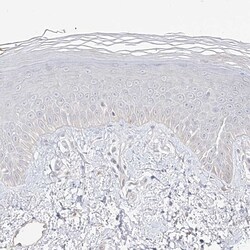

PA5-57300 IHC

Full details

Method: